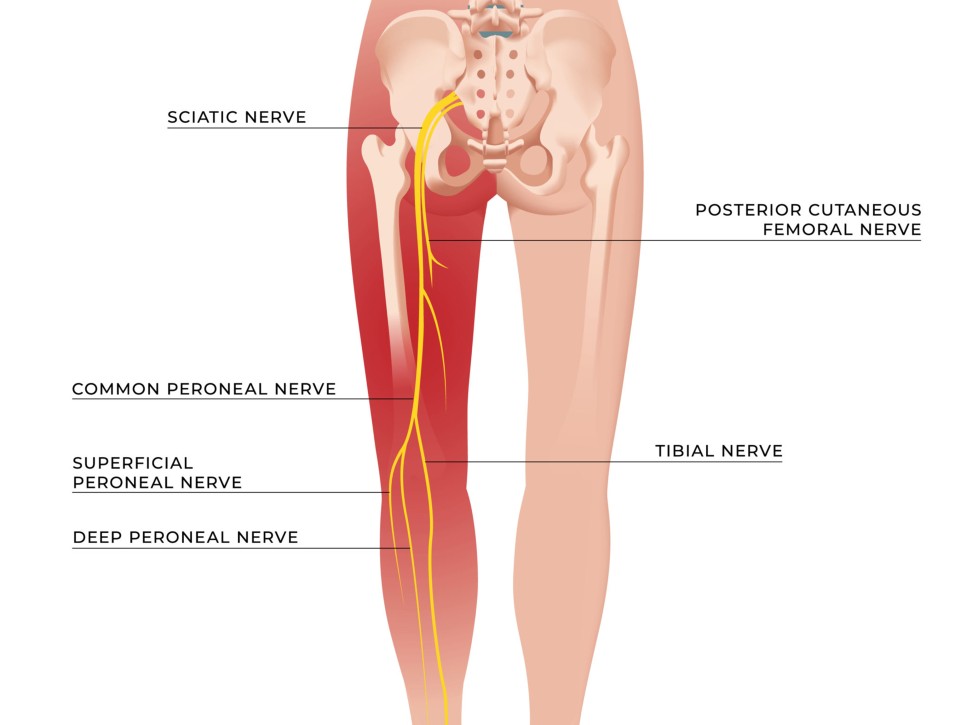

좌골은 의자에 앉았을 때 바닥에 닿는 부위이고 좌골신경은 좌골 안쪽을 지나 다리에 연결되는 신경근이 모인 말초신경입니다. 좌골 신경통은 허리와 엉덩이에서 다리로 이어지는 통증을 말합니다.

좌골을 지나 다리로 이어지는 좌골신경은 엉덩이 및 허벅지 바깥쪽에서 시작하여 종아리 바깥쪽/뒤에 띠 모양으로 이어지는 통증이 일반적입니다.

좌골신경통은 꼬리뼈와 천골 사이에 붙어서 고관절골로 이어지는 이상근과 관계가 있을 수 있습니다. 이상근증후군은 좌골신경통의 증상 중 하나로, 신경이 엉덩이에 눌려 종아리와 다리까지 통증이나 감각 이상이 발생합니다.